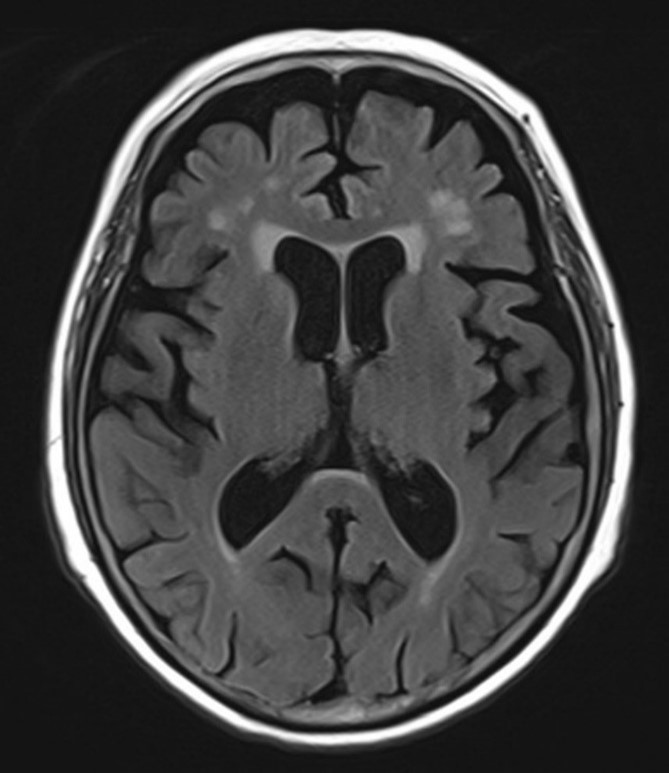

그림8.jpg 촬영 일시: 2025.06.15

<Fig 1. 뇌 MRI>

영상에서는 급성 뇌경색 같은 병변은 없었지만

연령에 비해 뇌위축이 상당히 진행되어 있었고

인지기능 검사에서도 유의한 점수 저하가 관찰되었거든요.